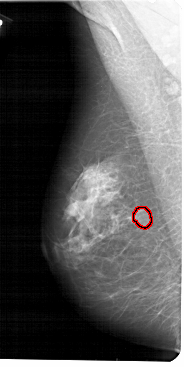

A_1512_1.LEFT_MLO

LEFT_MLO LINES 5491 PIXELS_PER_LINE 2746 BITS_PER_PIXEL 12 RESOLUTION 43.5 OVERLAY

FILE: A_1512_1.LEFT_MLO.OVERLAY

TOTAL_ABNORMALITIES 1

ABNORMALITY 1

LESION_TYPE MASS SHAPE OVAL MARGINS CIRCUMSCRIBED

ASSESSMENT 3

SUBTLETY 4

PATHOLOGY BENIGN

TOTAL_OUTLINES 1

BOUNDARY